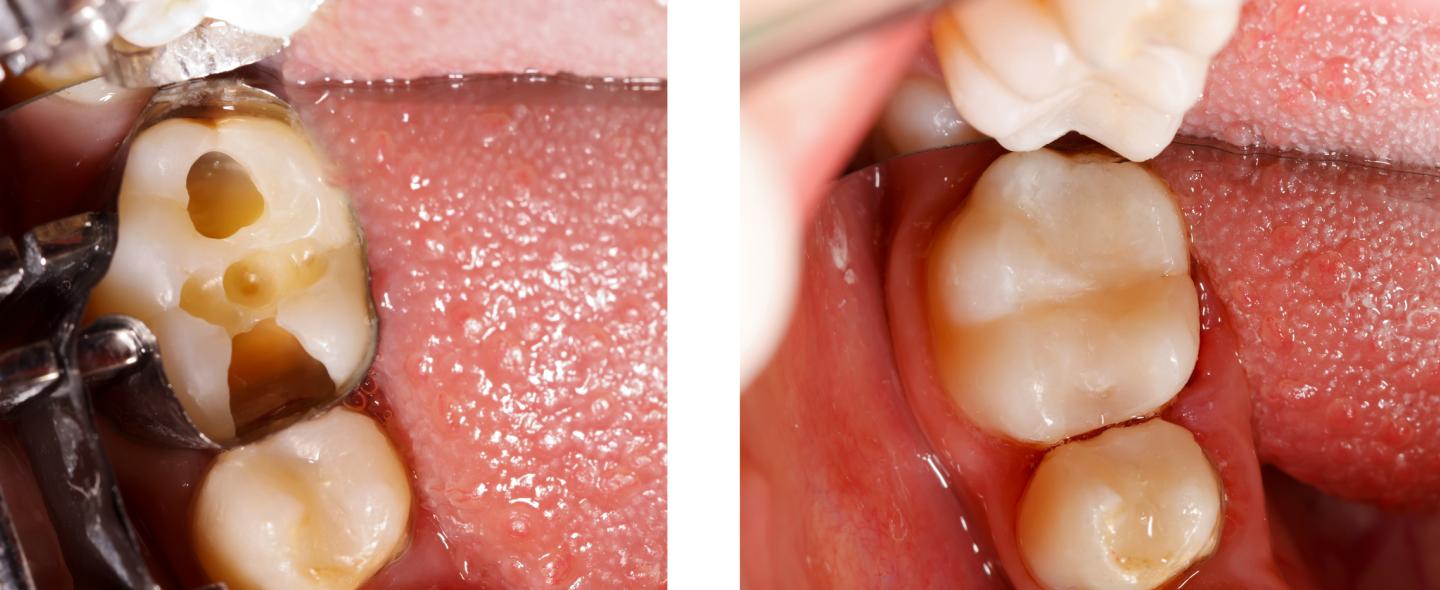

Jos kariesvaurio on edennyt kiilteestä syvemmälle hammasluuhun, hammas täytyy paikata.

Reikiintyneen hampaan paikkaus aloitetaan poistamalla karieksen tuhoama eli karioitunut hammaskudos. Jos karies on ehtinyt vaurioittaa hammasluuta vain vähän, vaurioitunut alue voidaan usein poistaa käsi-instrumenteilla, ilman poraa.

Useimmiten vaurioitunut hammaskudos poistetaan kuitenkin poraamalla nopeakierroksisella turbiiniporalla ja hitaammin pyörivällä mikromoottoriporalla. Joskus voidaan käyttää myös laseria.

Onkalo, josta vaurioitunut hammaskudos on poistettu, käsitellään erityisillä valmisteilla, jotta paikka-aine kiinnittyy hampaaseen. Käsittelyaineiden annetaan yleensä vaikuttaa hetki hampaan pinnalla, minkä jälkeen ne huuhdellaan tai kuivataan.

Kun paikka on kiinnitetty hampaaseen ja kovetettu sinisellä valolla, se muotoillaan yleensä vielä mikromoottoriporalla purentaan sopivaksi hampaan muotoja mukaillen.

Paikan sopivuus purentaan tarkistetaan purentafolion avulla. Folio asetetaan ylä- ja alahampaiden väliin, ja potilasta pyydetään tekemään erilaisia purentaliikkeitä. Paikkaa muotoillaan, kunnes se on purentaan sopiva. Lopuksi paikan pinta viimeistellään.